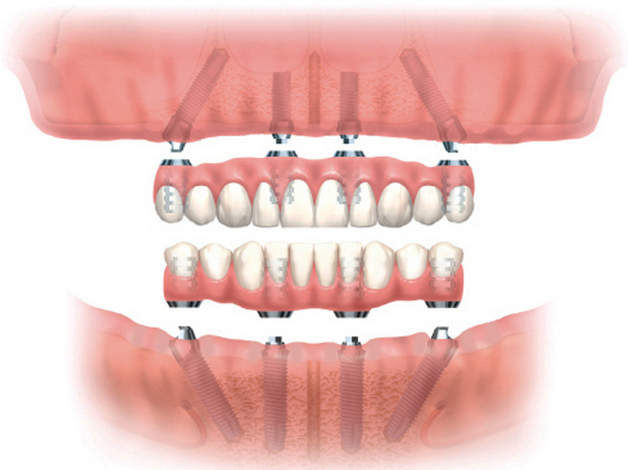

All-on-4 — протезирование на имплантах «все на четырех»

Метод All-On-4 является разработкой знаменитого португальского ученого по имени Пауло Мало, который провел множество успешных клинических экспериментов. Его изобретение позволяет восстановить два полных зубных ряда пациентам, которые по различным причинам утратили все свои зубы. Причем, данный результат достигается всего за одного посещение стоматолога. Кроме того, способ «Все на четырех» дает возможность пациентам принимать любую пищу, улыбаться и вести активные беседы без какого-либо дискомфорта сразу после завершения операции.

Суть этого метода имплантации сводится к размещению имплантантов в челюсти специальным образом: одна пара вживляется в область переднего отдела, а вторая — около «пятерок» с наклоном в 45 градусов. Затем на вживленные имплантаты устанавливают предварительно изготовленные зубы, воссоздающие полный зубной ряд всего за одну процедуру.

По утверждениям специалистов, методика All-On-4 подходит абсолютно всем, кто утратил свои натуральные зубы и вынужден пользоваться съемными протезами, обладающими не слишком надежной фиксацией. Также такой способ не имеет ограничений по возрасту. И, хотя в нынешнее время ему можно найти сразу несколько альтернатив, «Все на четырех» превосходит все эти методы тем, что является протезированием на имплантах без синус лифтинга, то есть не требует длительных и травматичных операций, связанных с обязательной подсадкой кости к вживленным ранее имплантатам.

Практические исследования показывают, что All-On-4 может служить порядка нескольких десятилетий, а при необходимости заменить отдельный зуб, процедура не займет много времени.

В линейке системы — имплантаты для различных типов и размеров кости, имеют высокий уровень первичной стабилизации и остеоинтеграции. Подходят для комплексной и классической имплантации. На системах можно осуществить протезирование по протоколам «Все-на-4», «Все-на-6». Возможна как винтовая, так и цементная фиксация оропедических конструкций.